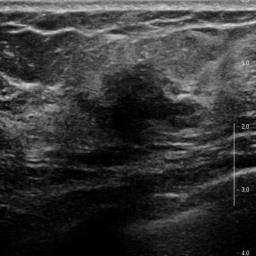

Ultrasonography is an important routine examination for breast cancer diagnosis, due to its non-invasive, radiation-free and low-cost properties. However, it is still not the first-line screening test for breast cancer due to its inherent limitations. It would be a tremendous success if we can precisely diagnose breast cancer by breast ultrasound images (BUS). Many learning-based computer-aided diagnostic methods have been proposed to achieve breast cancer diagnosis/lesion classification. However, most of them require a pre-define ROI and then classify the lesion inside the ROI. Conventional classification backbones, such as VGG16 and ResNet50, can achieve promising classification results with no ROI requirement. But these models lack interpretability, thus restricting their use in clinical practice. In this study, we propose a novel ROI-free model for breast cancer diagnosis in ultrasound images with interpretable feature representations. We leverage the anatomical prior knowledge that malignant and benign tumors have different spatial relationships between different tissue layers, and propose a HoVer-Transformer to formulate this prior knowledge. The proposed HoVer-Trans block extracts the inter- and intra-layer spatial information horizontally and vertically. We conduct and release an open dataset GDPH&GYFYY for breast cancer diagnosis in BUS. The proposed model is evaluated in three datasets by comparing with four CNN-based models and two vision transformer models via a five-fold cross validation. It achieves state-of-the-art classification performance with the best model interpretability.

翻译:超声波分析是乳腺癌诊断的一个重要常规检查,原因是其非侵入性、无辐射和低成本的特性。然而,由于其内在局限性,它仍不是乳腺癌的第一线筛选测试。如果我们能够精确地通过乳房超声图像诊断乳腺癌(BUS),它将是一个巨大的成功。我们提出了许多基于学习的计算机辅助诊断方法,以实现乳腺癌诊断/感官分类。然而,其中多数方法需要事先确定性能模型,然后对ROI内部的跨值进行分类。常规分类支柱,如VGG16和ResNet50等,可以在没有ROI要求的情况下实现有希望的分类结果。但是这些模型缺乏可解释性,从而限制了其在临床实践中的使用。在本研究中,我们提出了一个新的无乳腺癌诊断模型,在超声波图像中进行解释性特征描述。我们利用了先前的解剖学学学知识,即恶性肿瘤和良性肿瘤模型在不同组织层之间有着不同的空间关系,并提议采用状态解析法来编制这一先前的知识。拟议中的HOVer-Trans-Trading-Tradef-trainal Ex-deal-dealal-deal-deal-deal-degraphal-deal-deal-deal-deal-deal-deal disal disal-dal-dal-dal-dal-dal-deal-deal-dal-deal-deal-deal-dal-dal-dal-dal-dal-dal-dal-dal-dal-dal-dal-dal-dal-dal-I-dal-Iversal-dal-Ial-d-d-I-d-d-I-I-I-I-I-I-I-I-I-I-I-I-I-I-I-I-I-I-I-I-I-I-I-I-I-Ial-I-Ial-Ial-I-I-I-I-I-I-I-I-I-I-I-I-I-I-I-I-I-I-I-I-I-I-I-I-I-I-I-I-I-I-I-I-